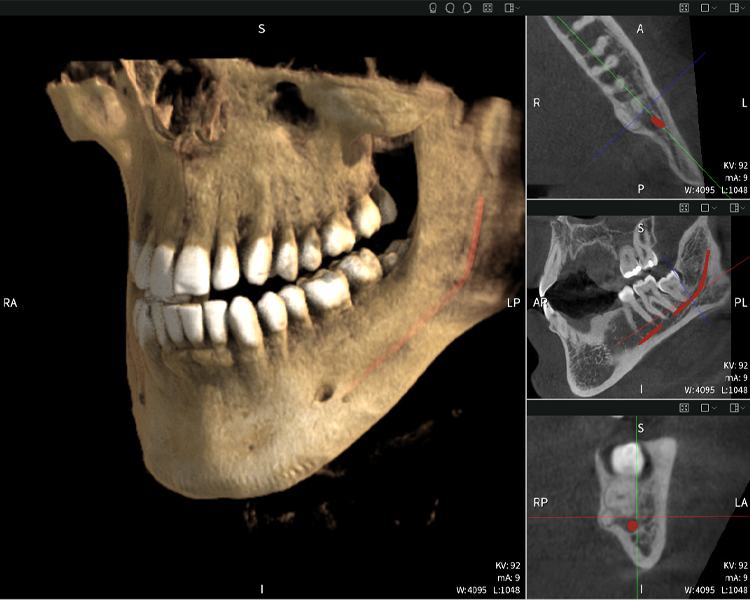

Las figuras b–d muestran varias vistas de una reconstrucción 3D de la mandíbula, proporcionando una visión general completa de la anatomía mandibular, la posición de los nervios en relación con los dientes y permitiendo evaluar la simetría y alineación dentaria.

La figura d muestra el diente 48 previamente tratado, con la corona retirada y las raíces dejadas en proximidad al nervio, lo que ilustra el alto riesgo de daño nervioso.